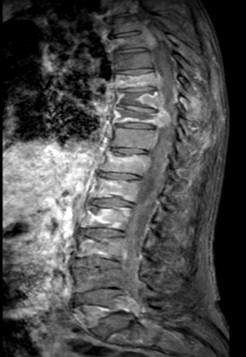

Resultados: Caso clínico 1. Se presenta el caso de un varón de 74 años con antecedentes personales de hipertensión arterial y dislipemia. Acude a consulta de Medicina Interna por lumbalgia de más de un mes de evolución y pérdida ponderal involuntaria de aproximadamente 10 kg. Visto por atención primaria y el servicio de Urgencias en varias ocasiones con diagnóstico de fracturas vertebrales, pautándose tratamiento analgésico. En la exploración física destaca tumoración pétrea laterocervical izquierda adherida a planos profundos e importante dolor a la palpación de apófisis espinosas de vértebras dorsolumbares. Durante su ingreso se realiza TC cérvico-toraco-abdominal y RM de columna dorsolumbar en el que se visualizan múltiples metástasis ganglionares, óseas, hepáticas y pulmonares. A pesar de analgesia de tercer escalón, el paciente precisa de radioterapia por clínica de compresión medular. Dentro del protocolo de estudio para filiar el tumor primario se evidencia una tumoración supraglótica izquierda estenosante que precisa de traqueotomía con toma de biopsia con resultado histológico de carcinoma escamoso mal diferenciado. Por la presentación infrecuente de diseminación, se realizó biopsia ecoguiada de una adenopatía cervical izquierda y de la apófisis transversa D11 con resultado en todas las muestras de carcinoma escamoso mal diferenciado. Durante su hospitalización, el paciente presentó una evolución tórpida complicándose con perforación de víscera hueca de origen no filiado por lo que se inició sedación falleciendo el paciente. Caso clínico 2. Varón de 77 años, sin antecedentes médicos de interés que acude a consulta de Medicina Interna remitido desde consultas de Otorrinolaringología por tumoración latero-cervical derecha filiada histológicamente como metástasis de carcinoma mal diferenciado de probable tumor de origen digestivo. El paciente asocia pérdida ponderal de aproximadamente 8 kg y aparición de adenopatías laterocervicales derechas de un año de evolución. En exploración física destaca tumoración de 2 o 3 cm en región IB-II derecha, móvil y no dolorosa la palpación sin otros hallazgos reseñables. Se completa estudio con TC abdominopélvico y estudio endoscópico mediante gastroscopia y colonoscopia sin identificarse evidentes lesiones neoplásicas. Se solicita PET-TC con reporte de foco hipermetabólico y asimetría en base de lengua derecha sugestivo de neoplasia primaria. Se contacta con el Servicio de Otorrinolaringología para realización de biopsia con resultado histológico de carcinoma de células escamosa pobremente diferenciado. En la actualidad, el paciente está en espera de tratamiento quirúrgico, como primera opción terapéutica.